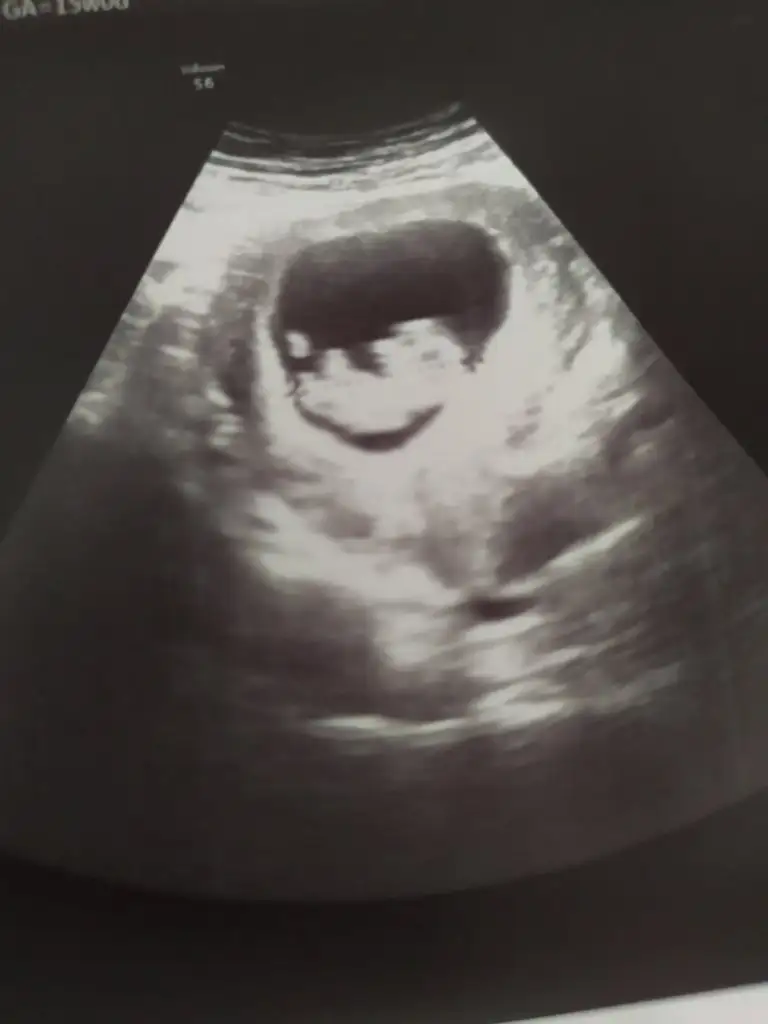

prenses gibi duruyor kuzum sen ne hissediyorsunEki Görüntüle 3051273 Eki Görüntüle 3051273 bana da yorum yapabilir misiniz rica etsem karından bakıldı :)

Evet canım karından, ilk öğrendiğimden beri herkes erkek dedi ama ben kız istiyorum umarım kız olur8 hafta 5 gün sanırım karındanbence Prenses